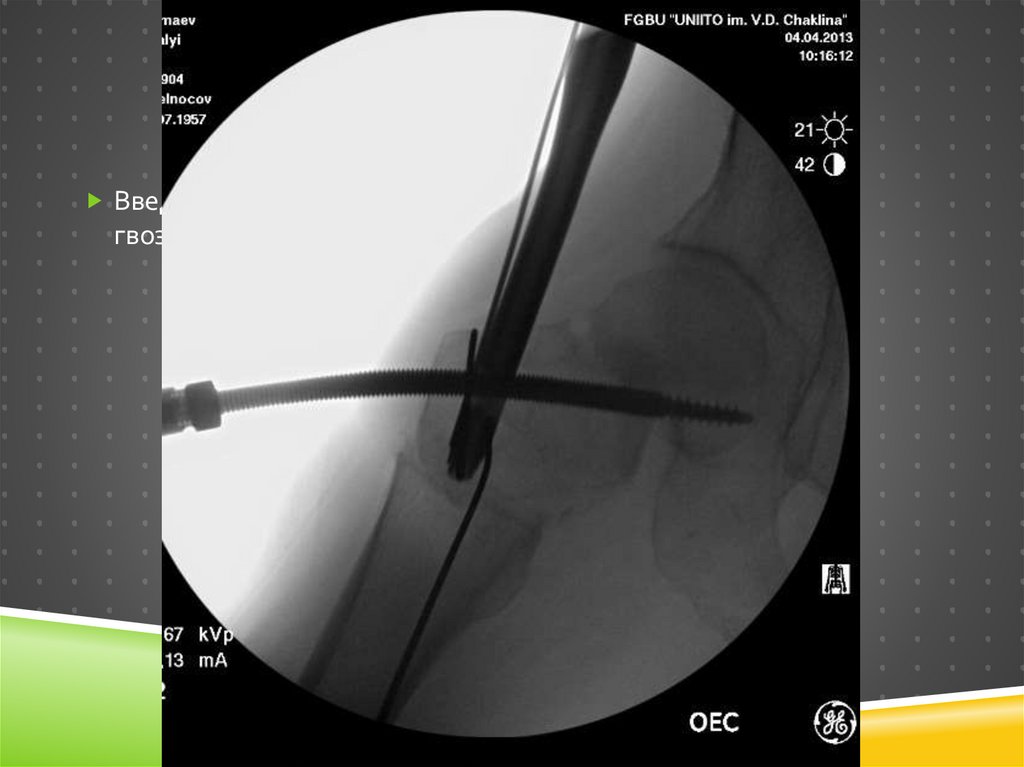

121.

Ревизионный остеосинтез

Уже более правильный

имплантат

Все проблемы решены?